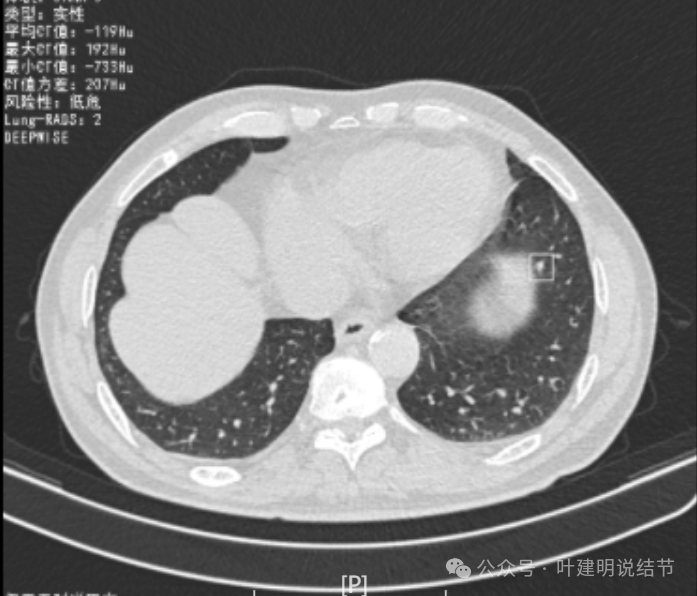

这是冠状位、矢状位与轴位的影像。

增强纵隔窗见病灶内部的密度好像低于周围区域,像坏死。

邻近胸膜无牵拉,灶内有低密度区,局部有点状液性密度。邻近胸膜较为广泛的增厚或胸膜反应。

病灶与胸膜接触面宽,病灶内部密度较低。